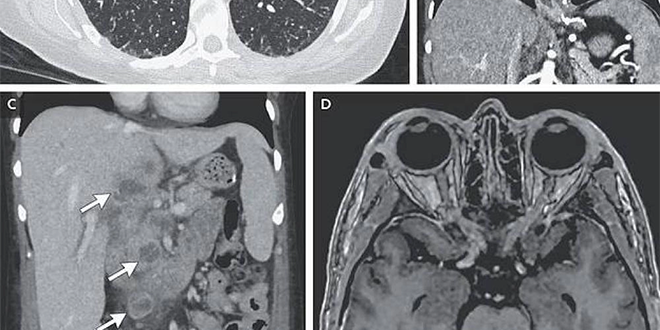

أظهرت الفحوص الشعاعية وجود عقيدات صغيرة منتشرة في الرئتين، إلى جانب آفات في الكبد والغدد اللمفاوية والبنكرياس والدماغ. وبعد 9 أسابيع، أكدت التحاليل المخبرية إصابتها ببكتيريا المتفطرة السلية المسببة لمرض السل، في شكل نادر يعرف بالسل المنتشر الذي يصيب أعضاء متعددة من الجسم.